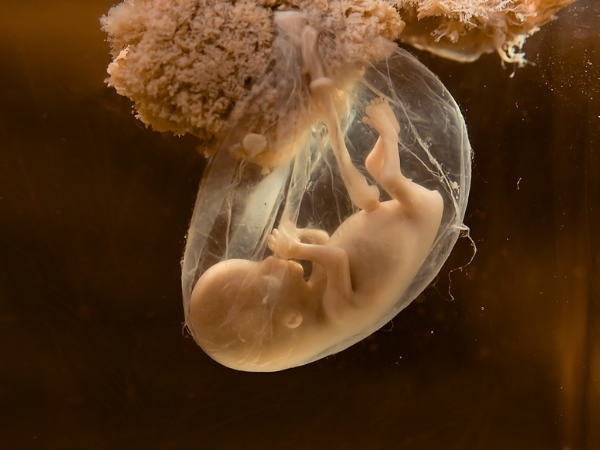

जानिए कब पहली बार गर्भ में भ्रूण का दिल धड़कता है?

जब अल्ट्रासाउंड के मॉनिटर पर बच्चे का दिल दिखाई देता है और धड़कनें चलती रहती हैं। लेकिन ऐसी बहुत सी चीजें हैं जिनकी आप कल्पना भी नहीं कर सकती।

आप बच्चे को जन्म देने वाली हैं! अधिकतर महिलाओं के लिए मातृत्व का ये एहसास पहली बार अल्ट्रा साउंड के साथ होता है।

भ्रूण की हार्टबीट, प्रिग्नेंसी, जन्म और बाद में भी आपके बच्चे के स्वास्थ्य में महत्वपूर्ण भूमिका निभाती है। ये अच्छी बात है कि आपके बच्चे की दिल की धड़कनों को देखने की तकनीक कई जानकारियाँ प्रदान करती है, गर्भावस्था के दौरान सब ठीक रहे और जन्मजात दिल की बीमारियों का जल्दी ही पता चल जाता है।

तीसरा सप्ताह: निषेचन के 22 दिन बाद भ्रूण का दिल बनना शुरू होता है, लेकिन इसकी धड़कनें सुनाई नहीं देती हैं।

पांचवा सप्ताह : भ्रूण का हार्ट चेम्बर विकसित होना शुरू होता है।

छठा सप्ताह: हार्ट रेट 100-160 बीट्स पर मिनट (बीपीएम) हो जाती है। इस समय आप अल्ट्रासाउंड मॉनिटर पर धड़कनें देख सकते हैं।

आठवा सप्ताह: बच्चे की हार्टबीट में एक स्थिर रिदम होती है।

दसवां सप्ताह: हार्ट रेट 170 बीपीएम तक बढ़ जाती है और जन्म के समय 130 बीपीएम के लगभग स्थिर हो जाती है।